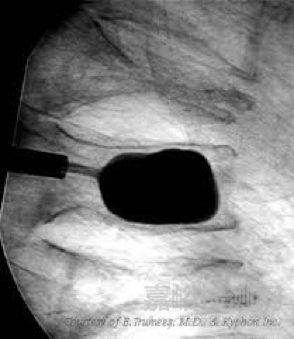

椎體成形術- 1997年美國骨科醫(yī)生Mark Reiley研制出一種可膨脹性椎體撐開球囊(Inflatable Bone Tamp),該技術采用經(jīng)皮穿刺椎體內(nèi)球囊擴張的方法使椎體復位,在椎體內(nèi)部形成空間,減小了注入骨水泥時所需的推力,并使骨水泥不易過多彌散。